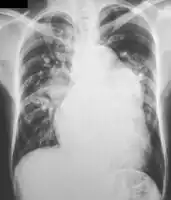

A chest X-ray may be taken, which reveals overall heart size (as a reflection of the combined mass of the cardiac chambers) and the appearance of blood flow to the lungs. A small PDA most often accompanies a normal-sized heart and normal blood flow to the lungs. A large PDA generally accompanies an enlarged cardiac silhouette and increased blood flow to the lungs.